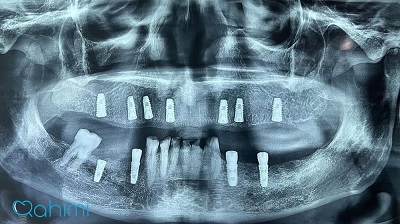

دکتر حامد رحیمی متولد سال ۱۳۶۷ می باشند.ایشان در سال ۱۳۸۵ موفق به ورود به رشته دندانپزشکی دانشگاه علوم پزشکی تهران شدند و در سال ۱۳۹۱ فارغ التحصیل گردیدند.در سال ۱۳۹۴ پس از گذراندن طرح دوره دکتری عمومی در استان قم موفق به قبولی در رشته جراحی لثه و ایمپلنت دانشکاه علوم پزشکی تهران گردیدند.ایشان از سال ۱۳۹۷ و پس از کسب بورد تخصصی به عنوان عضو هیات علمی دانشگاه علوم پزشکی قم مشغول هستند.

- ایمپلنت

- پیوند استخوان

- پیوند سینوس

- ایمپلنت فوری

- ایمپلنت دیجیتال

- پیوند لثه

- جراحی لثه

- جراحی افزایش طول تاج

- لیفت لثه

- لیزر

- جراحی و کشیدن دندان